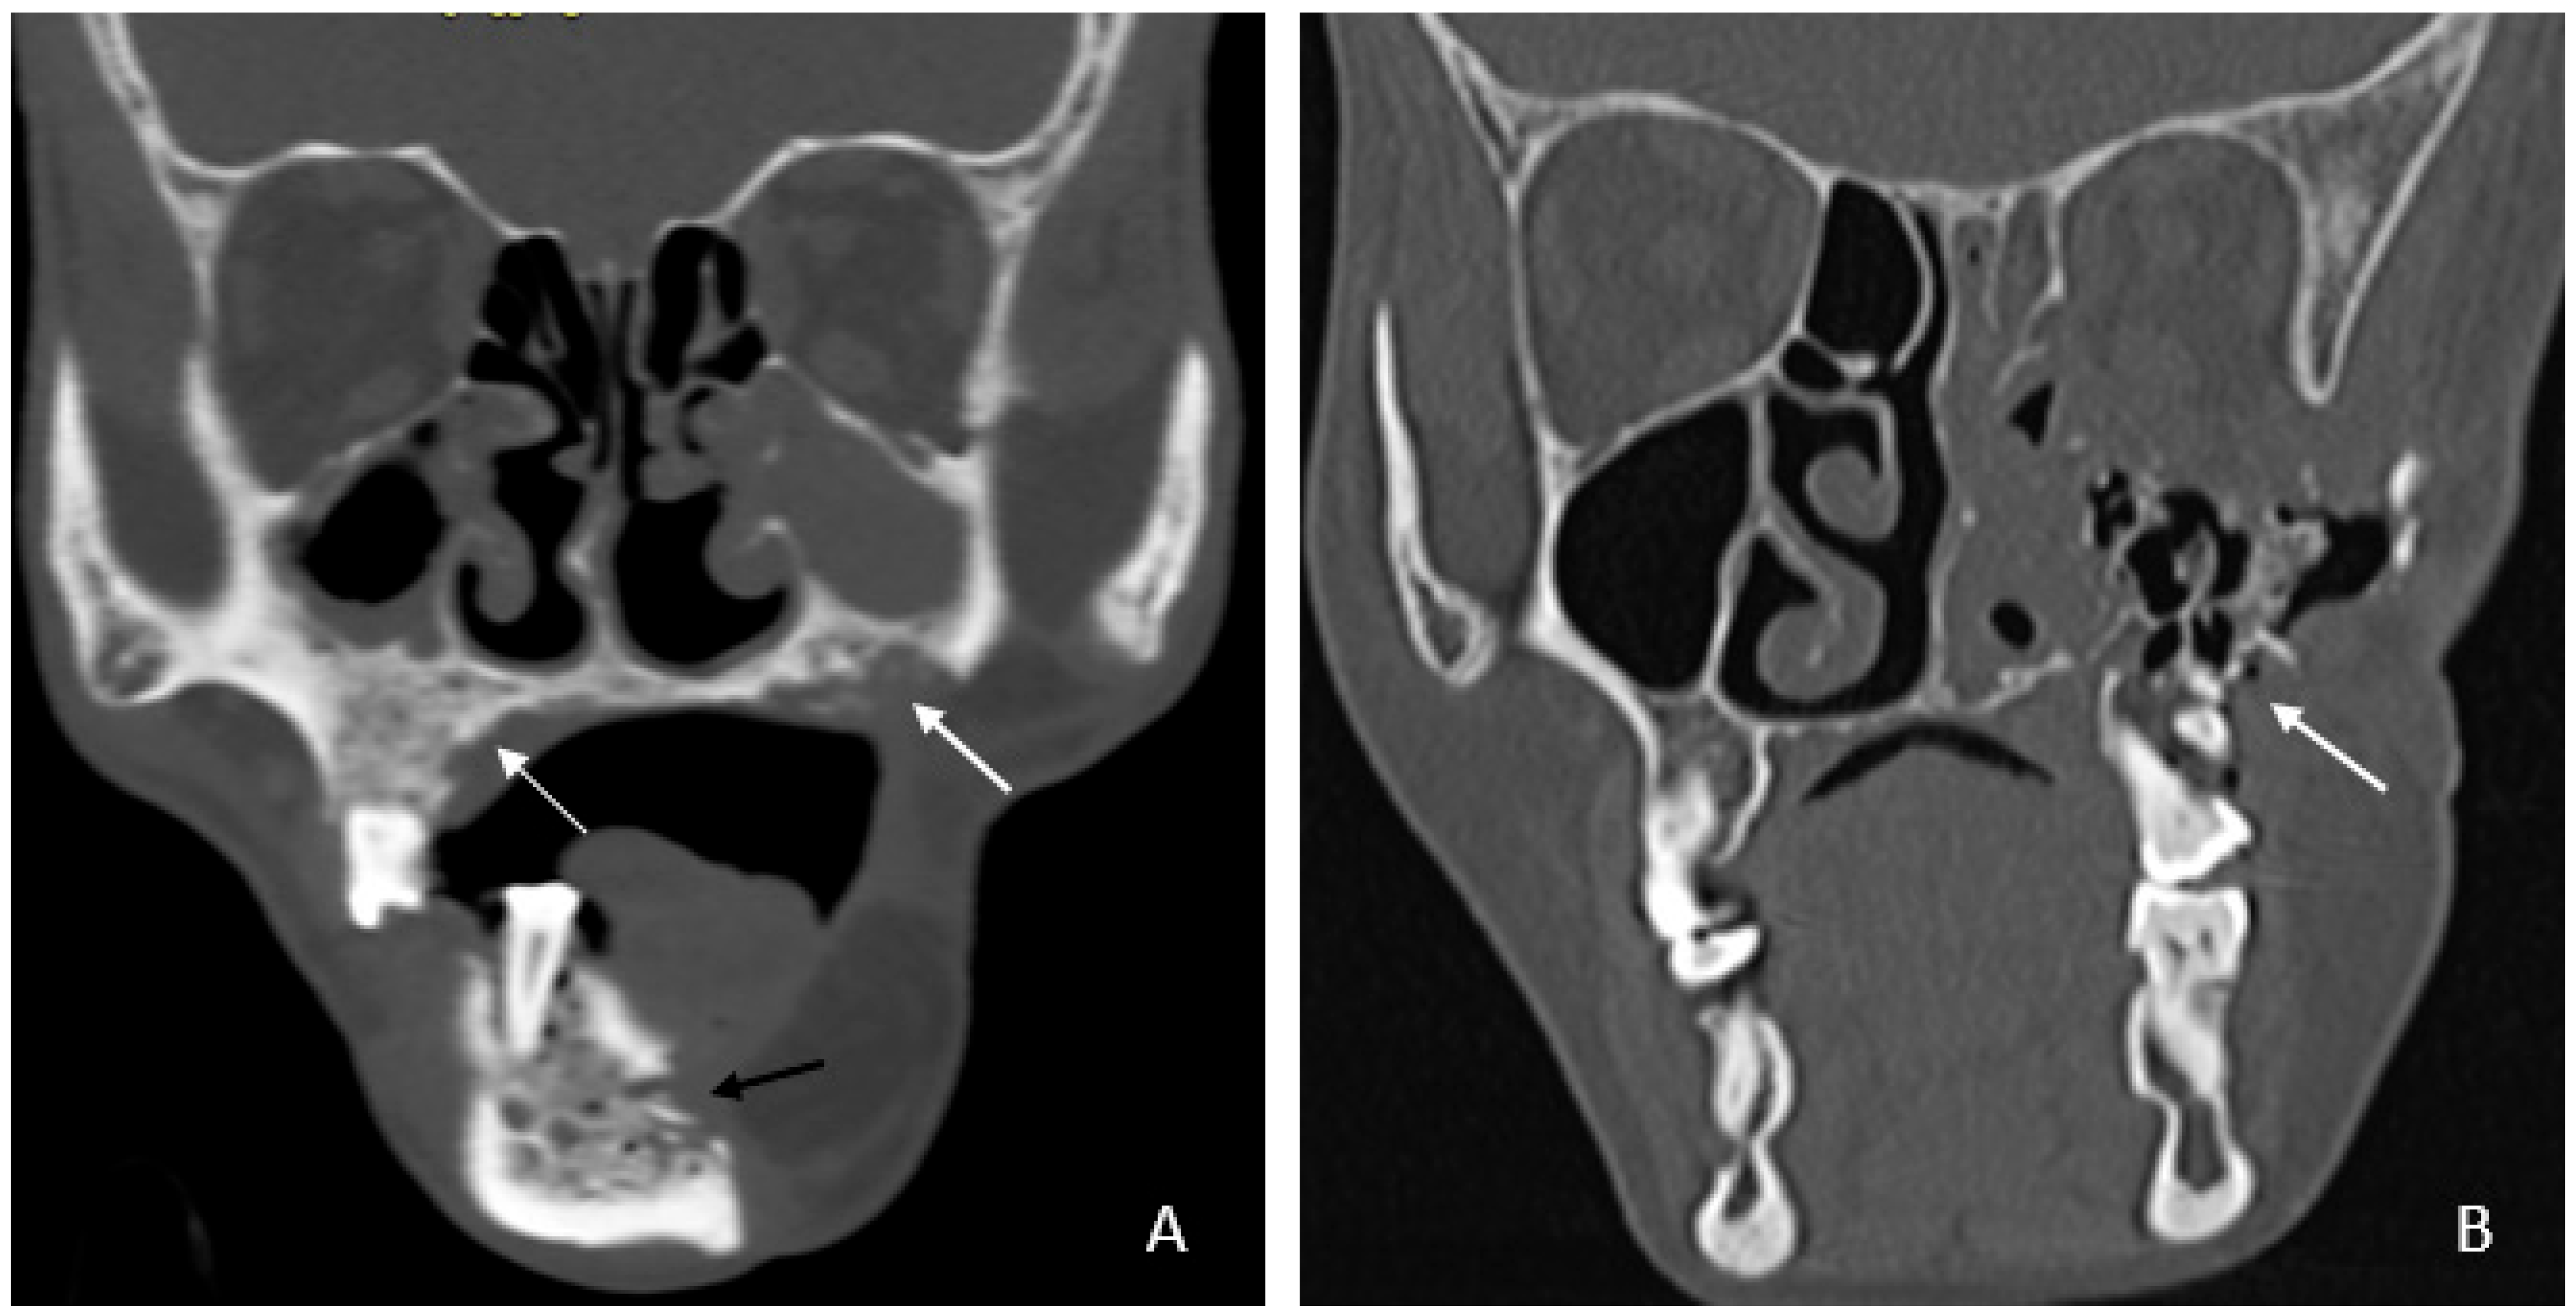

• Bone involvement: 18 patients had only mandibular ORN, while 16 had combined mandibular and maxillary involvement (Figure 1B). Isolated maxillary ORN was observed only once (Figure 1A). Bilateral maxillary involvement alone was not observed.

Figure 1. (A) Coronal CT image showing involvement of bilateral upper alveolus (white arrow) and mandible with areas of cortical erosion, trabecular thickening, and sclerosis (black arrow). (B) Coronal CT image showing extensive ORN of the left maxilla—seen as destruction and collapse (arrow).

• Mandibular involvement was categorized as focal (<1/4th of hemi-mandible) in 63% or diffuse (larger area) (Figure 2A,B). Thirteen patients (37%) showed abnormalities extending across the midline. No significant associated soft tissue was noted compared to the bone erosion, and it was predominantly isoenhancing compared to the muscle (97%).